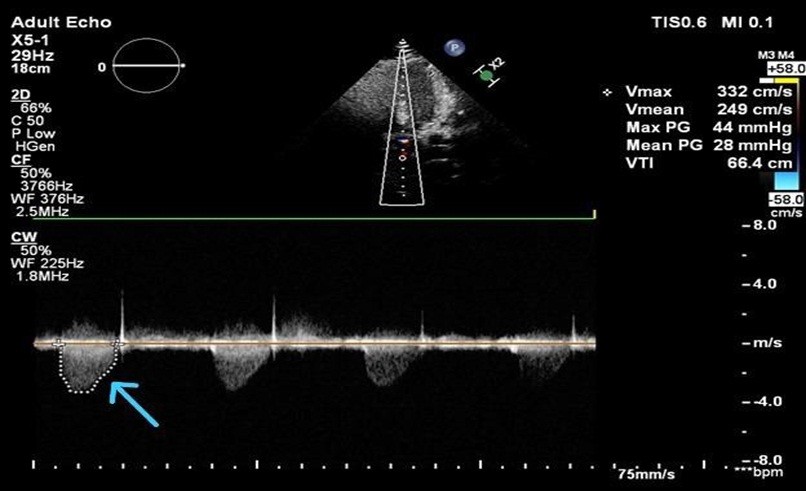

Cardiovascular imaging (echocardiography and cardiac magnetic resonance imaging, cMRI) confirmed SVAS. Transthoracic echocardiography revealed situs solitus, levocardia, supravalvular aortic gradient 44 mmHg, and mild concentric left ventricular hypertrophy (Fig. 3, 4).

Figure 4. Transthoracic echocardiography (apical view) with continuous-wave Doppler interrogation of the left ventricular outflow tract demonstrating high-velocity systolic flow across the supravalvular aortic region (arrow). Peak velocity (Vmax) is 3.32 m/s with a calculated peak pressure gradient of 44 mmHg and mean gradient of 28 mmHg, consistent with hemodynamically significant supravalvular aortic stenosis.